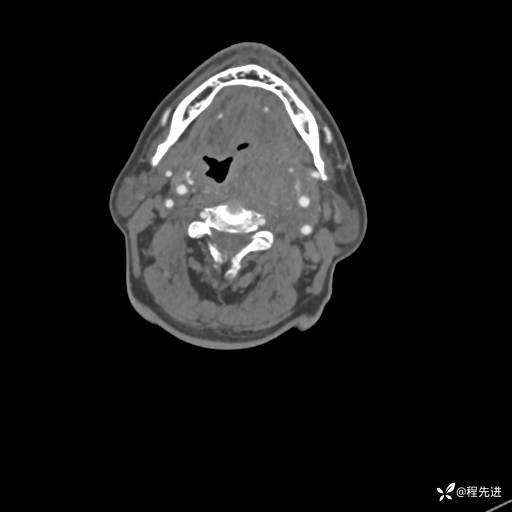

CT平扫:

CT增强:

动脉期:

静脉期: